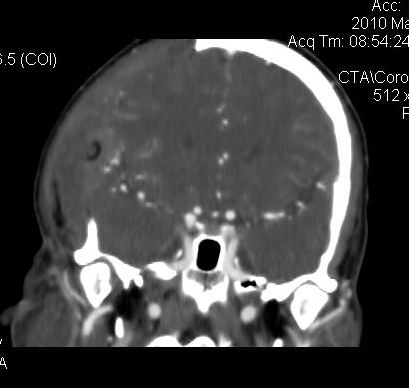

男.60岁,渐进性意识不清,ct检查双侧额颞顶部硬膜下血肿,开颅术后行脑血管cta,大脑中动脉起始部见一瘤状血管扩张。请各位老师留下宝贵意见

太常见了,报动脉瘤就可以

符合动脉瘤表现。

符合动脉瘤表现。

动脉瘤。

颅内动脉瘤。

后重建做得不是很好看,要将维蒂斯环充分显示,最好在增加一个mip。这样不好定位。

小动脉瘤

典型

符合动脉瘤的表现

动脉瘤

符合动脉瘤表现。

小动脉瘤

典型